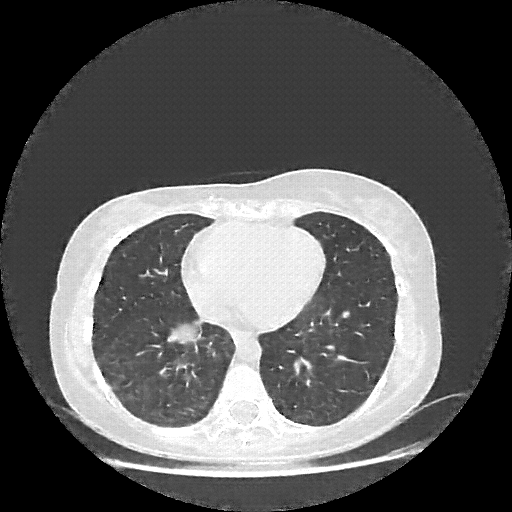

Generated VENOUS CT scan (A→B translation)

Full window (WL 1023.5, WW 4095 β†’ Low βˆ’1024, High +3071)

Lung window (WL -600, WW 1500 β†’ Low βˆ’1350, High +150)